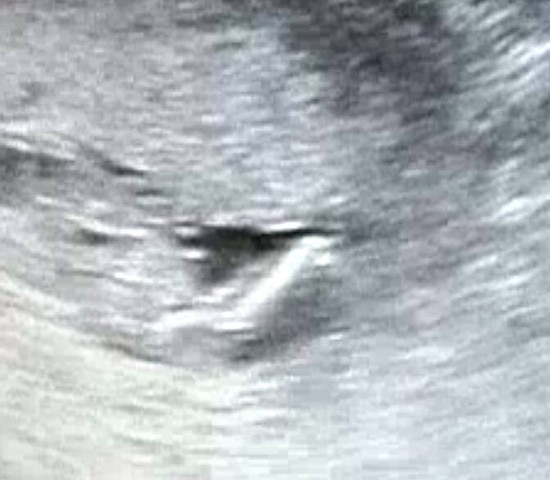

SSW, in der 15 konkretisierte es sich dann und in der Gechlecht bei Nackenfaltenmessung Ja, bei mir wurde in der 13Wo von der Ärztin während der Untersuchung zur Nackenfaltenmessung das Geschlecht bestimmt, es solle zu 80%ein Mädchen werdenSicherer wird es aber erst bei der FeindiagnostikNun bin ich in der 26SSW und es ist dabei. Ein Junge ist aus der richtigen Position gut zu erkennen Bei einem Mädchen müsste der Arzt nur drei weiße Striche (Falten) erkennen Besser ist es die Bestätigung in der SSW zu bekommen Wenn dein Gefühl so stark ist, kann es vieleicht doch ein Junge sein Mädchen outing 163 ssw 8 März 19 um 1256 Letzte Antwort 9. 3 striche waren da xD das heißt doch mädchen oder?.

Das sieht also schon nach Mädchen aus Dachte ich mir auch logischerweise, aber Google mal 3StricheUltraschall Merkwürdig Ich hab zwei Mädels, und da sah man zwei parallele Striche und der FA hat auch kommentiert, dass die zwei Striche das klassische USMädchenmerkmal sind. Diese Frage beschäftigt viele Paare, sobald sie erfahren, dass sie ein Baby erwarten. Hallo, für ein Mädchen sprechen 3 echoreiche parallele Streifen Vor der 14 SSW ist das kaum auszumachen NT von 1,7 mm ist im Normbereich.

Wenn dein Baby beim Ultraschall mitspielt, kannst du jetzt herausfinden, ob es ein Mädchen oder Junge wird Dennoch gilt Es haben sich schon viele Ärzte geirrt und nach der 16 SSW oder gar nach der Geburt festgestellt, dass das Mädchen, ein Junge ist – oder anders herum. Hallo, für ein Mädchen sprechen 3 echoreiche parallele Streifen Vor der 14 SSW ist das kaum auszumachen NT von 1,7 mm ist im Normbereich. Na die drei striche sollen die schamlippen darstellen Ich habe bisher immer nur eine vermutung zu einem mädchen outing bekommen ich hoffe bei meinem nächsten Fa Termin in 3 Wochen, bekomm ich auch so ein bild mit drei strichen grüße fee und baby ssw.

Es waren 3 Striche zu sehen, was ja bekanntlich für ein Mädchen spricht;. Ab SSW 15 kann man das Geschlecht des Babys im Ultraschall erkennen Wann wissen wir, ob es ein Mädchen oder ein Junge ist?. Ab der 16 SSW sind die äußeren Geschlechtsorgane deines Babys genügend entwickelt, um im Ultraschall sehen zu können, ob du ein Mädchen oder einen Jungen erwartest In den Wochen zuvor konnte hier nur spekuliert werden.

In der 16ssw,ssw und 23ssw hieß es Junge,dann in der 27ssw Mädchen und seitdem sieht man nichts mehr,könnten Hoden sein,aber da fehle der schnippel,könnten aber auch große schamlippen sein Keiner wagt eine Diagnose Haha. ULTRASCHALL IN DER SSW 21 I WIRD ES WIRCKLICH EIN MÄDCHEN ?. Wenn 3 striche zwischen den Beinen zu sehen sind, dann sind das die striche der schamlippen Ergo Mädchen ) Antworten Like 1 dass diese drei striche auf ein mädchen deuten aber ich weiß, es ist noch sehr früh.